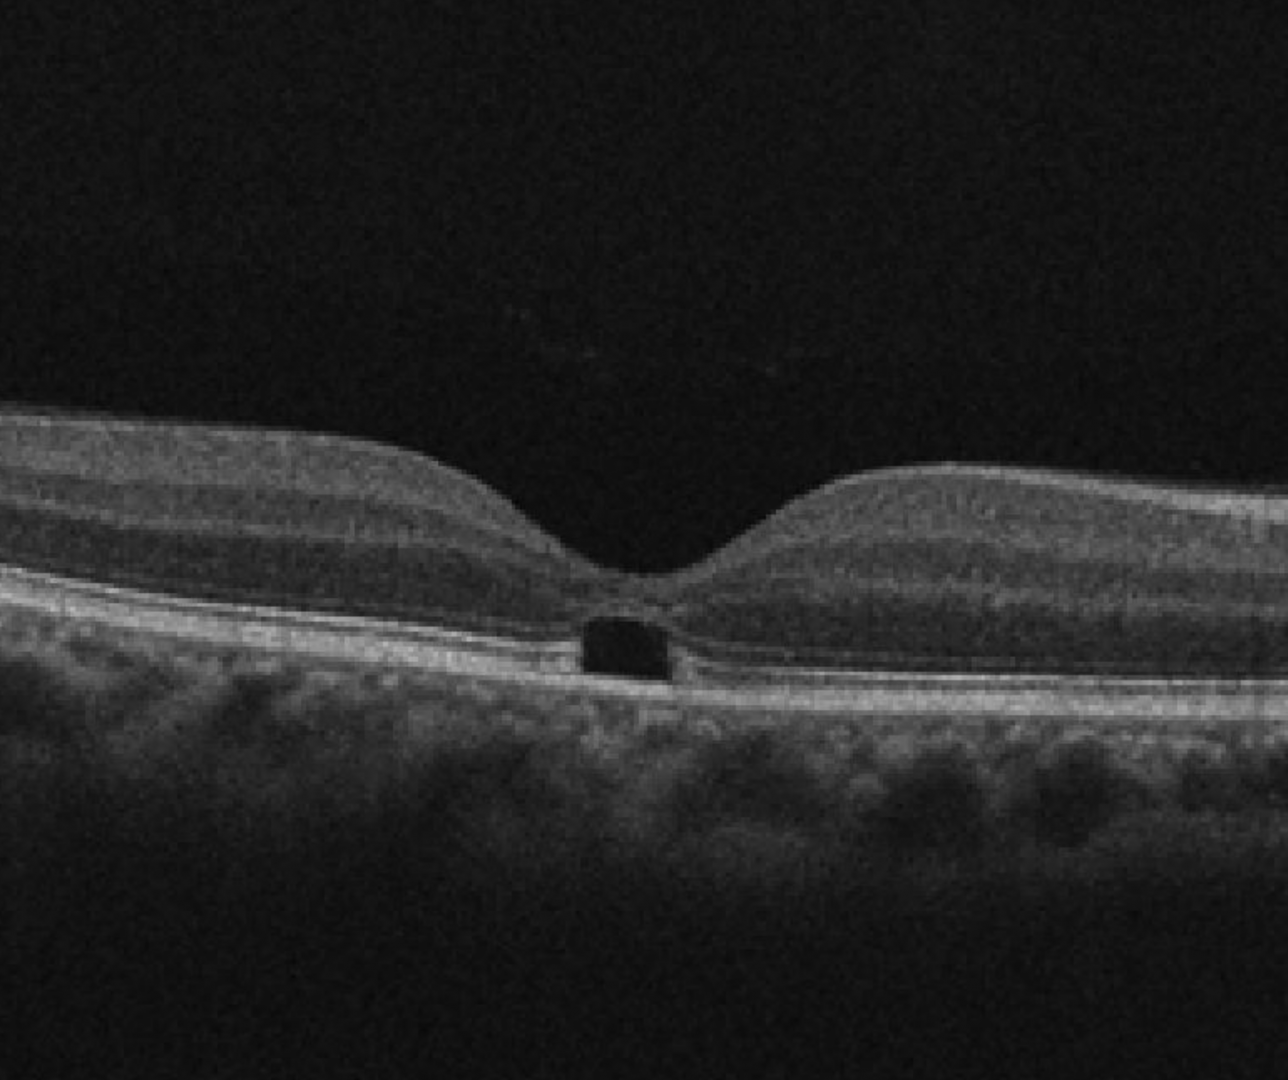

Clinically, bilateral yellow dots may be seen at the fovea. This corresponds to changes in the outer retinal layers on OCT which may be either hyper-reflectivity of the ellipsoid zone or a subfoveal hypo-reflectivity. Fundus autofluorescence is typically normal.

Cirrus OCT line scan (right macula)